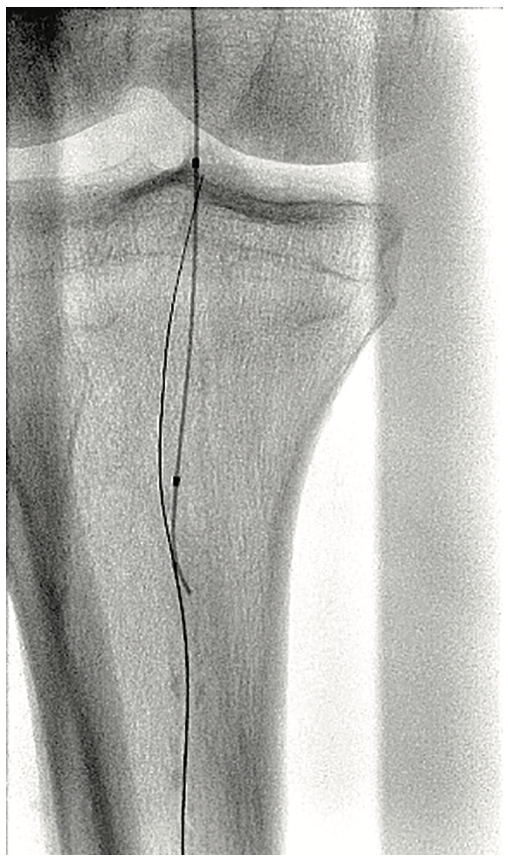

A 6 French (Fr) sheath was inserted into the right femoral artery in an antegrade fashion. An .035-inch x 90 cm Trailblazer (Medtronic) was inserted over an .035-inch x 180 cm Aquatrack guidewire (Cordis, A Cardinal Health company) and advanced into the right popliteal artery. Angiography was performed prior to surgical cut down of the posterior tibial artery (PT) (Figure 1). Access into the PT was made using a 4 Fr micropuncture pedal sheath (Cook Medical). An .014-inch Confianza guidewire (Asahi Intecc) was inserted and advanced into the PT. Using the stiff Confianza, a Viance Flexible CTO catheter (Medtronic) was advanced. When Viance extravasated from the PT, an Aquatrack wire and .035-inch Trailblazer were introduced and advanced in a antegrade manner. The Viance and Trailblazer could be visualized going in different directions (Figure 2). Using that image, the Viance was pulled back and repositioned to find the true lumen from the bottom to the top, using the guidance from the wire. The Confianza was readvanced after the true lumen was found, and Aquatrack was pulled back into the Trailblazer and eventually removed. The Confianza wire was advanced further into the .035-inch Trailblazer, and eventually pulled through the right femoral artery sheath in a retrograde fashion (Figure 3). The right femoral artery Trailblazer was removed. A TurboHawk SX-C atherectomy catheter (Medtronic) was used to debulk the plaque and achieve luminal gain from the popliteal artery into the tibioperoneal trunk (Figure 4). Drug-coated balloon angioplasty was performed using the IN.PACT balloon (Medtronic) into the popliteal artery (Figure 5). The TurboHawk was reinserted and advanced further down to the peroneal artery into the tibioperoneal trunk in order to establish luminal gain in the distal vessel. Final angiography revealed successful recanalization of the lower extremity vessels through the use of the antegrade/retrograde method, with distal access through the posterior tibial artery (Figure 6).